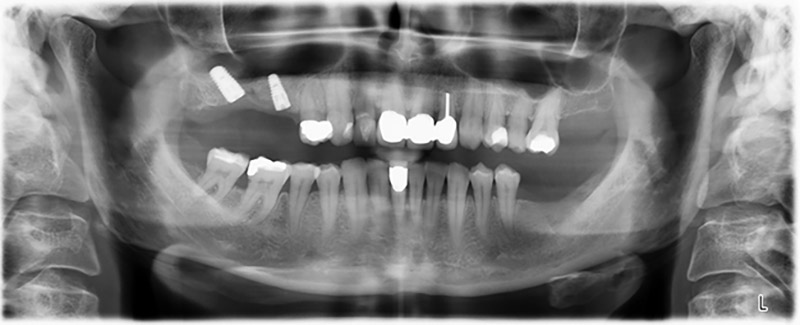

Immagine 20: Ortopantomografia dopo il trattamento